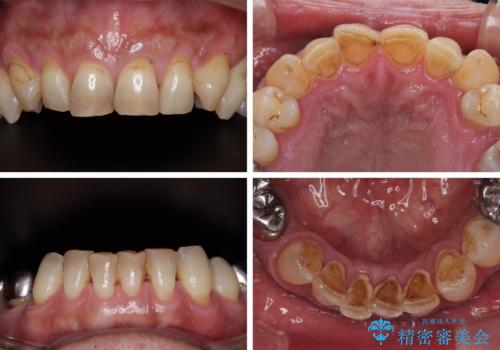

黄ばんだ前歯をきれいに 前歯の審美歯科治療

- 薬剤の影響で黄ばんでしまった前歯を気にして来院された患者様です。

お子様が大学を卒業され、経済的に余裕ができたとのことで、長年気にしていた前歯を綺麗にする決断をされたとのことでした。

奥歯の銀歯も気にはなるものの、口を開けたときに目立たないとのことで、上下ともに前歯を中心にオールセラミッククラウンにて補綴治療を行うこととしました。